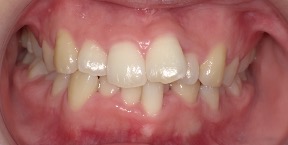

33歳女性のビフォーアフター

| 診断 | 空隙 |

| 治療方針 | 治療方針:前歯の咬合関係改善と空隙閉鎖を主な目的にて主にIPR(歯と歯の間をわずかに削合してスペースを獲得する方法)を組み込んだ動的矯正治療を行い、空隙、前歯咬合を改善後、保定を行う。臼歯部の咬合関係はプランの都合上維持することとした。 |

| 治療費 ※ | 67万8千円(診断、型取り、矯正中のメンテナンス、保定装置を含む料金) |

| 治療期間 | 6か月 |

| リスク | 1日20時間以上マウスピースを使用できない場合、歯が動かなかったり、想定しない誤差により不完全に終わる可能性がある。装着時や食事時に痛みを伴う。歯肉退縮や虫歯になるおそれがある。また、指導通りに装着できていない場合や適切なブラッシングが出来ていないとそのリスクが高くなる。歯根が短くなることがある。ごくまれに歯の神経が損傷してしまうことがある。過去にぶつけたり深い虫歯治療をしたことがあるとそのリスクはやや高くなる。矯正後には保定装置が必要。適切な使用ができない場合、後戻りの原因となる。将来的に歯並びが動いて再矯正が必要な場合がある。親知らずが正常に生えていない場合、その可能性がやや高くなる。 |